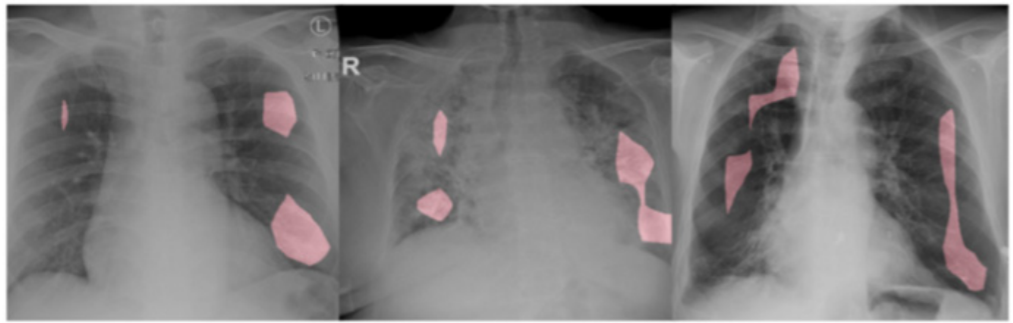

COVID-19 胸部X射线肺炎检测:DarwinAI开发了由AI驱动的解决方案COVID-Net CT,以快速,准确地检测患者的COVID-19,并使用OpenVINO进行了推理优化。